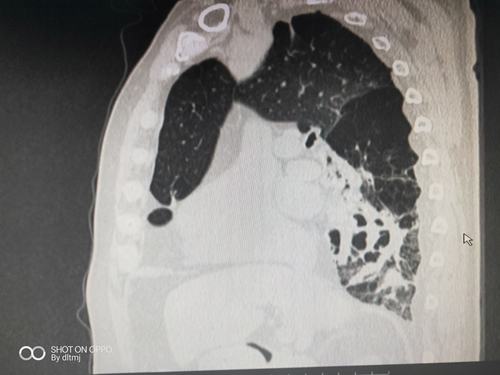

支气管扩张系列病例——呼吸影像群,余杭方建庆

支气管扩张的ct图片

支气管扩张图片

支气管扩张图片样子